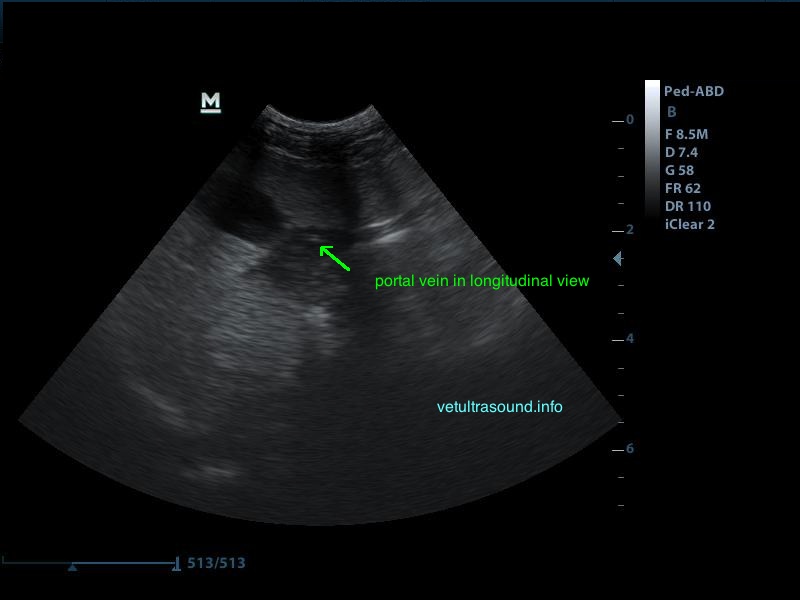

Αντίθετα στο τμήμα που δεν έχει γίνει εναπόθεση λίπους είναι εύκολη η απεικόνιση του τοιχώματος της πυλαίας φλέβας.